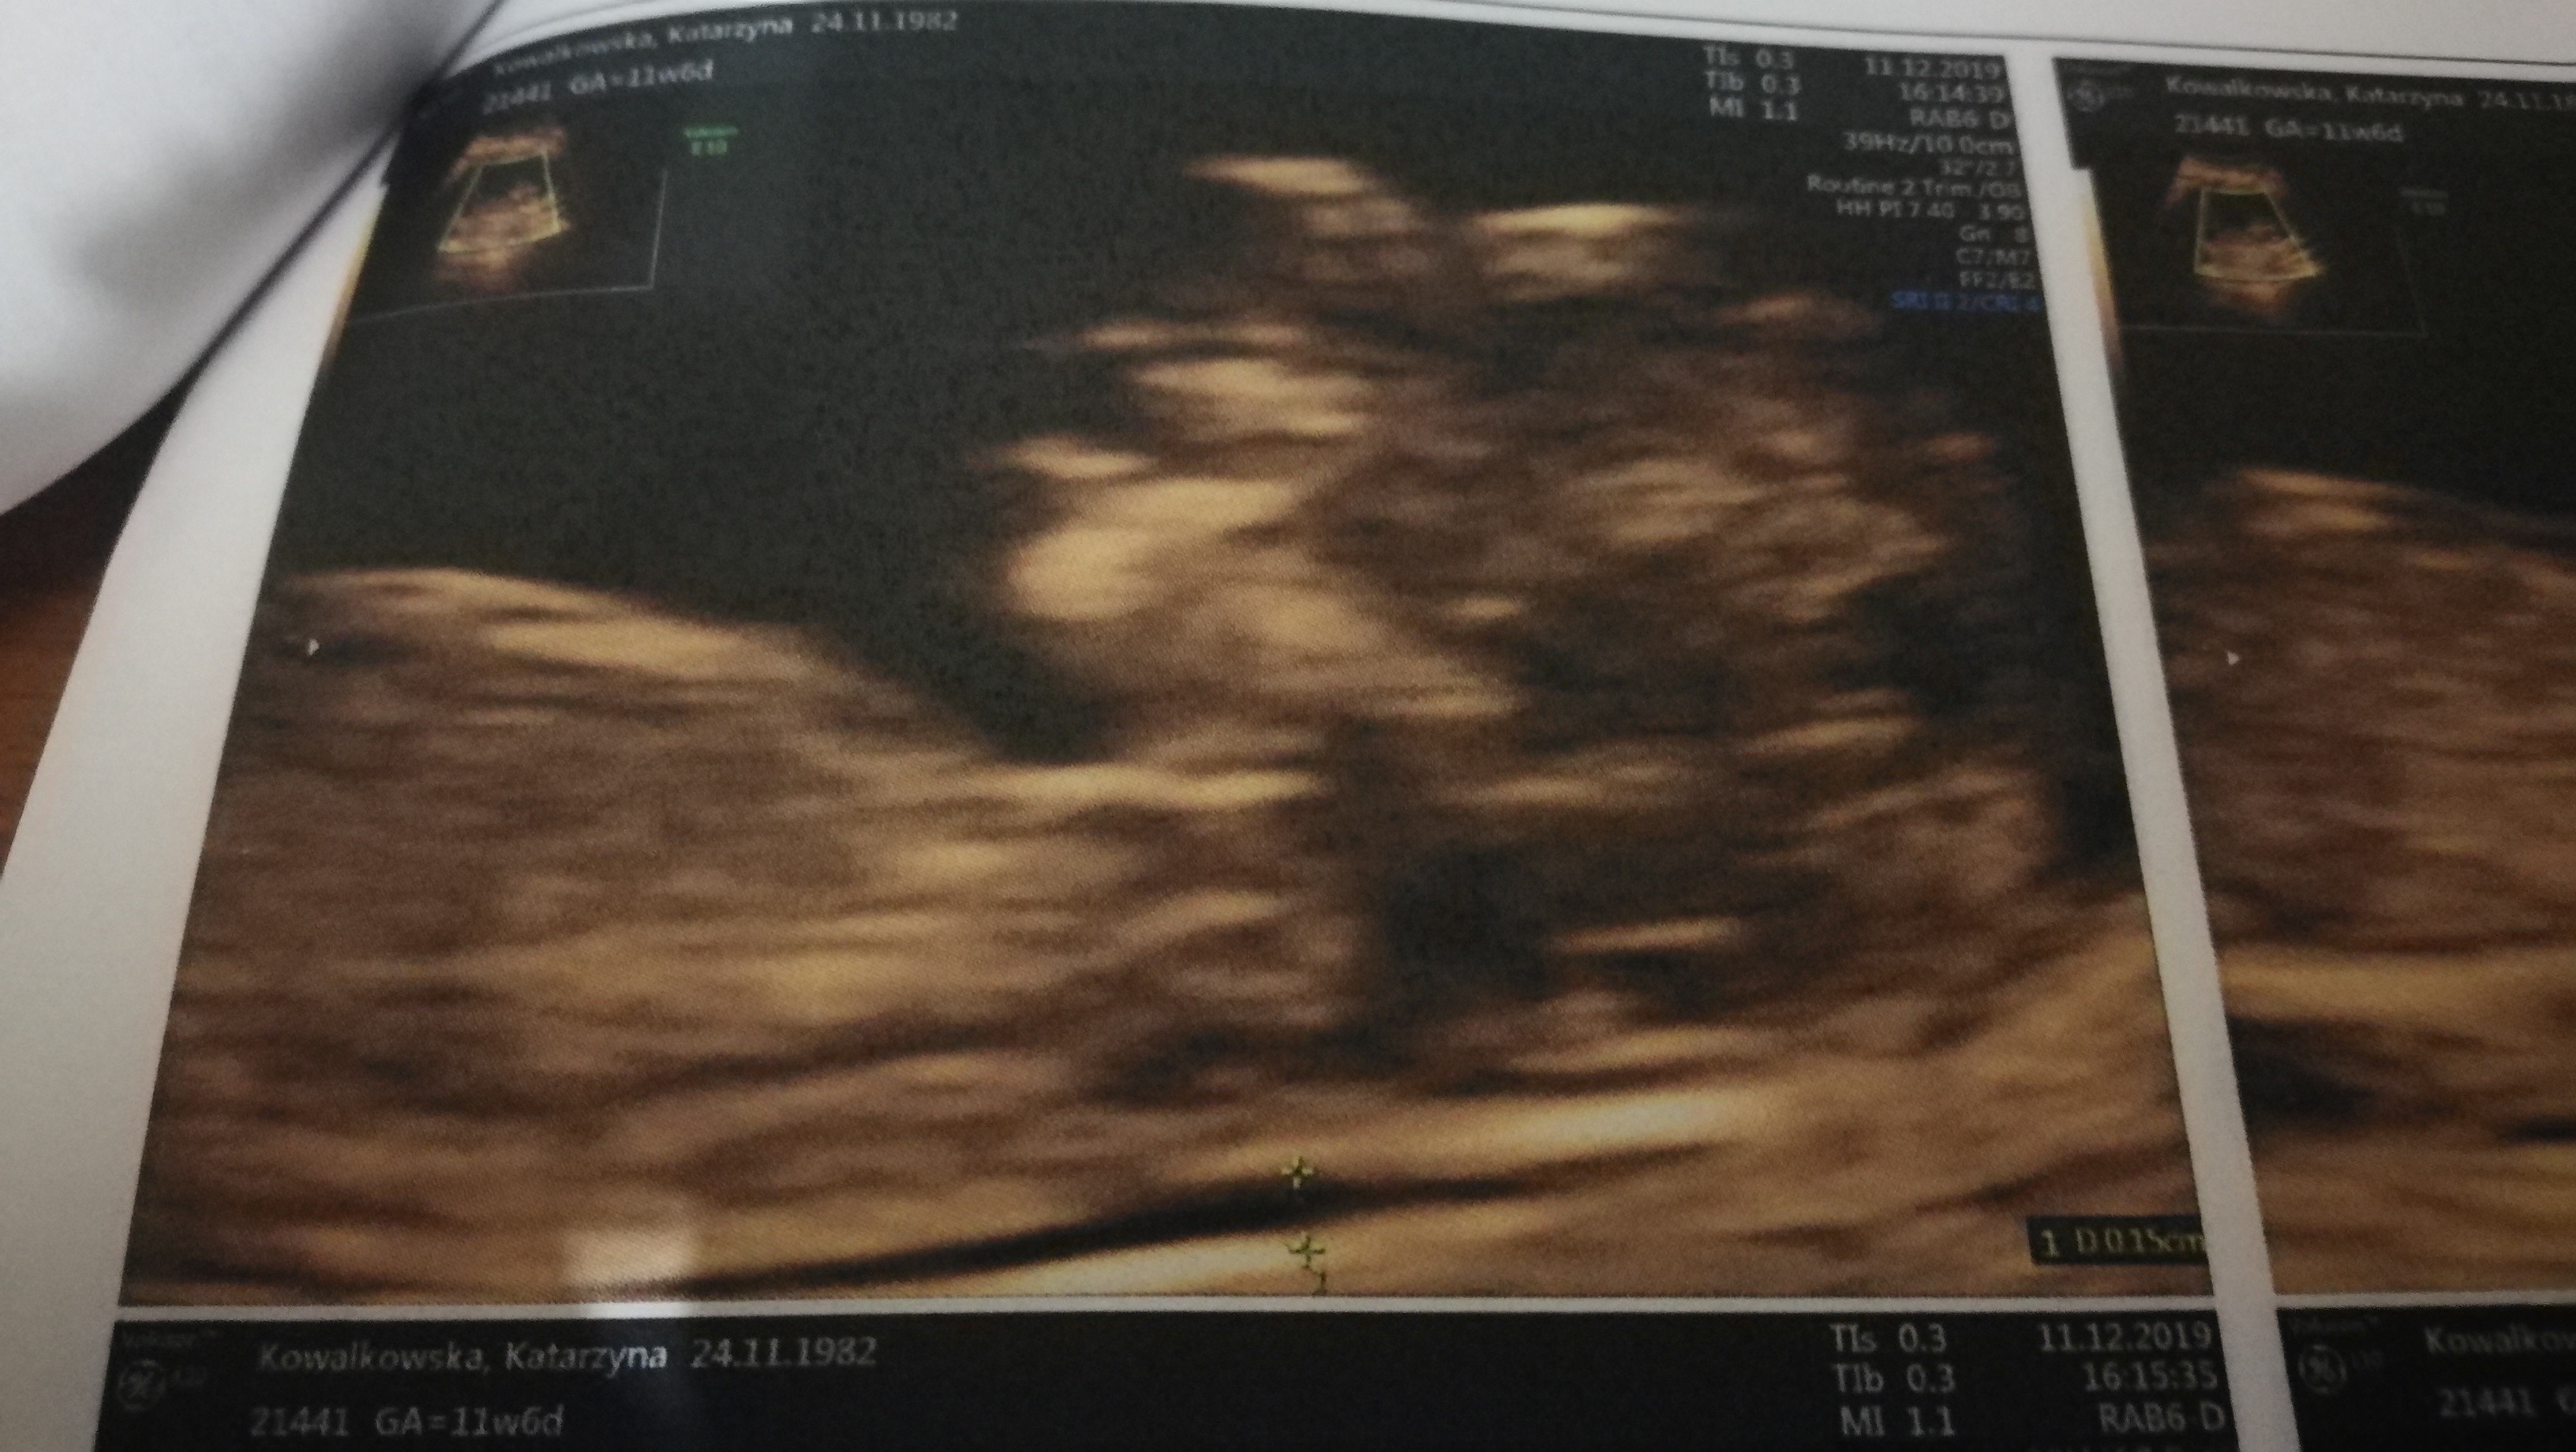

Jestem po badaniach prenetalnych wszystko ok z dzidziusiem. Co do plamien to mam nisko łożysko i mam nakaz nic nie robic i nie dźwigać.

Ale słyszałam serduszko i tak ładnie bylo go widać taki maluszek. 5.38 cm 😊

• IMG_20191211_175853.jpg

IMG_20191211_175853.jpg

937,4 KB · Wyświetleń: 130